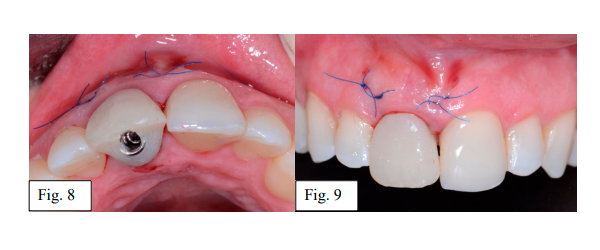

Por fim, o provisório foi instalado sobre o implante com morfologia côncava na área submucosa, definindo a zona subcrítica e o contorno da margem mucosa coronária delimitando a zona crítica (Fig. 8 e 9).